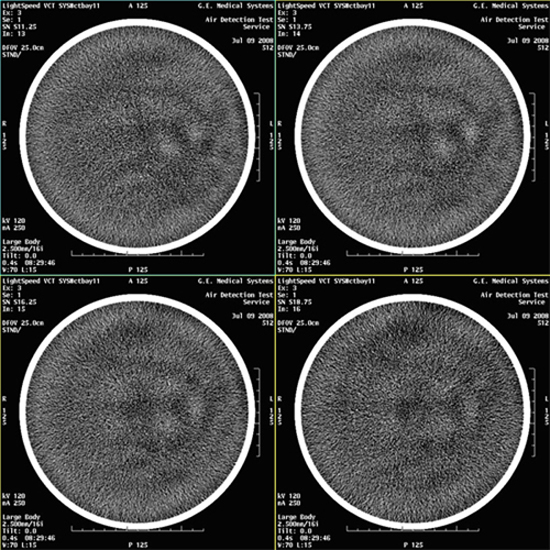

- Select VIEWER and review all images for

blotchy artifacts. (See Figure 1, Figure 2, and Figure 3). If an artifact is encountered, perform Tube Oil Cooling System Air Removal.note:

If air artifact exists, the air activity may be more significant in Images 13 through 16, 29 through 32, 45 through 48, and 61 through 64.

Figure 3. Images with Artifacts